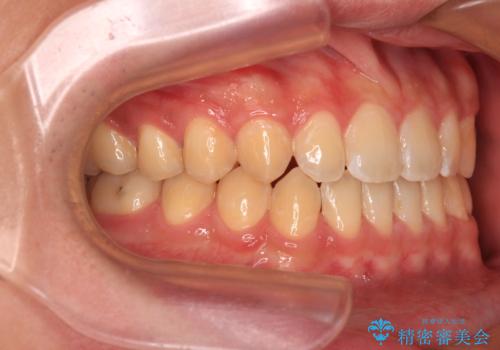

舌の突出癖がなかなか改善されず、治療期間は当初予定よりも大分長くなりました。

装置除去を予定していた日に、油断されたのか1mmほどのスペースを作ってしまったため、除去が3ヶ月延長されたことで、舌のトレーニングの重要性を理解していただきました。

装置除去後もトレーニングを継続されているようで、後戻りによるスペースは今のところ認められておりません。